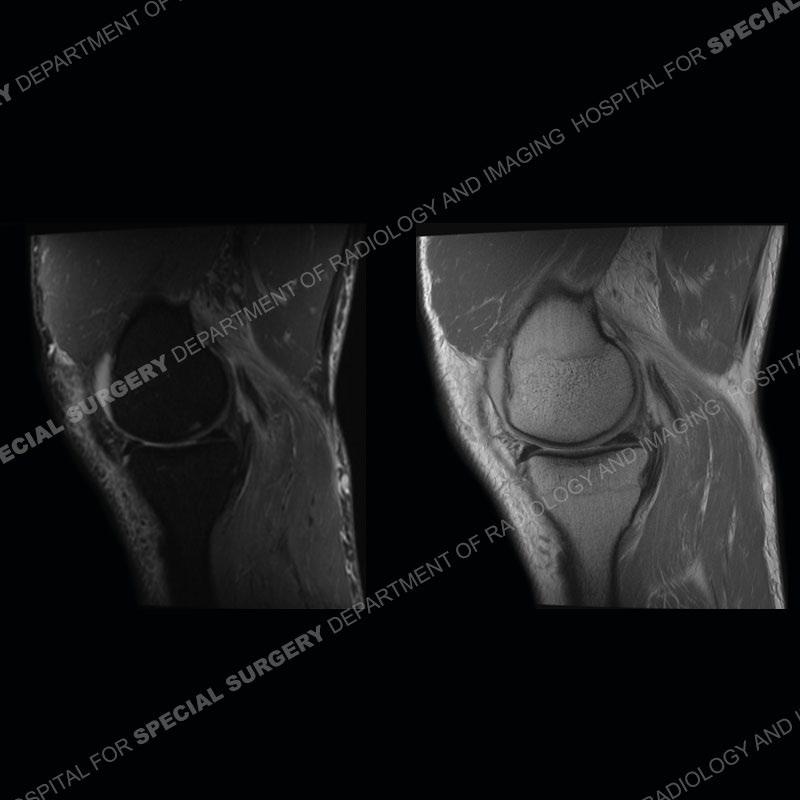

Findings

The radiographs show degenerative change of the medial compartment and a varus knee, but they are not germane to this case. No acute bony injury is present. The MRI shows edema of the posterior medial knee/soft tissue and a focal area of a partially disrupted low signal structure. The details are kept at a minimum in the findings of this case on purpose.

Diagnosis: Partial Disruption Medial Head Gastrocnemius (MHG)

The findings were kept purposefully vague as identifying the structures early on takes away a lot of the diagnosis. An uncommon entity and one of which we do not see a lot. Enthesopathic changes and tendinosis are seen as are distal MHG injuries, but proximal tears are rarely present. This case highlights a number of points. One, it almost always comes down to anatomy. Perhaps not a structure we normally spend too much time on, except save for diagnosing a Baker’s cyst, but knowing where this structure and all structures exist in all three planes is imperative. Second, when you think you are making a “call” or finding that you have never made before, step back and think is this just the abnormal presentation of a common pathology. That situation arises much more frequently. Third, if you look at it once, twice, and probably a third time and are confident in your odd or very rare diagnosis, stick to your guns. Especially, when it comes down to anatomic structures, the proof will be in the images.

Fourth, use all imaging planes and different pulse sequences to make your diagnosis. The edema highlighted in this case can be seen as the obscuration of fat on the PD images but is much easier to perceive as the high signal on the IR pulse sequences. The actual disruption of the MHG myotendinous junction is only able to be seen on the axial images. On the sagittal and coronal images, we get a sense something is wrong but hard to be exact. Lastly, when you look at a study and something just seems off (as I would say the sagittal and coronal images do with that dark band of tissue posteriorly), listen to yourself and go through the study slowly and meticulously. Most of the time you will find you were right, and something indeed is present.